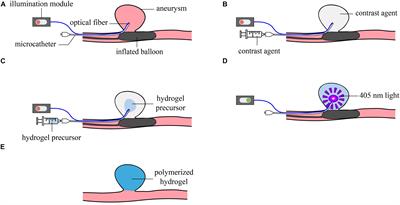

Poupart O., Conti R., Schmocker A., Pancaldi L., Moser C., Nuss K. M., Sakar M. S., Dobrocky T., Grützmacher H., Mosimann P. J., and Pioletti D. P., Pulsatile Flow-Induced Fatigue-Resistant Photopolymerizable Hydrogels for the Treatment of Intracranial Aneurysms, Front. Bioeng. Biotechnol., Vol. 8, January 2021. |

Poupart O., Schmocker A., Conti R., Moser C., Nuss K. M., Grützmacher H., Mosimann P. J., and Pioletti1 D. P., In vitro Implementation of Photopolymerizable Hydrogels as a Potential Treatment of Intracranial Aneurysms, Front. Bioeng. Biotechnol., April 2020. |